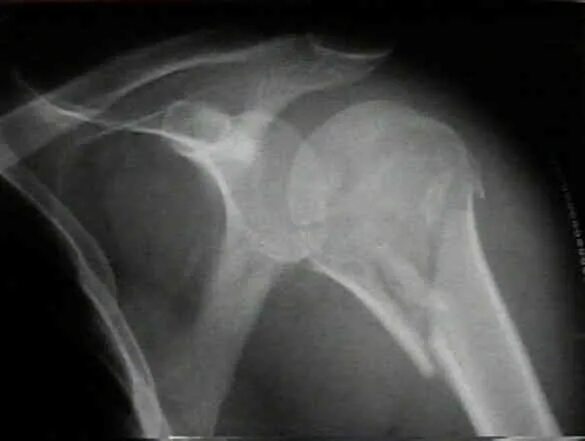

Перелом шейки плеча у пожилых